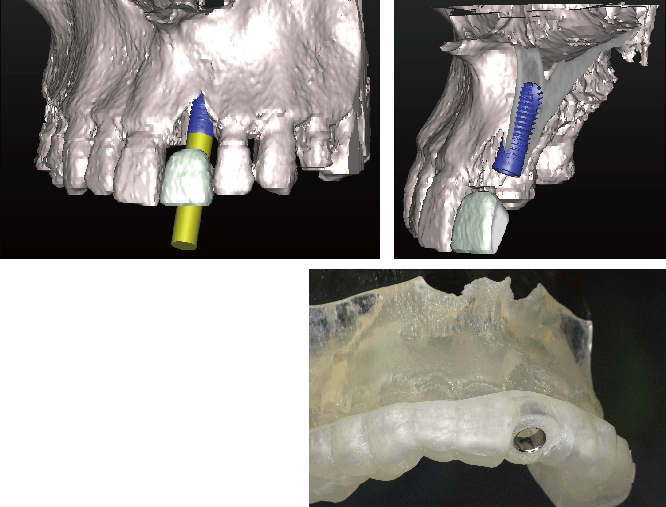

当院では安心安全なインプラント治療をより確実に行うために、すべてのインプラント治療で3Dコンピューターシミュレーションシステム「シンプラント プロ」で歯科CT画像からデータ解析を行い、サージガイドを作成するコンピューターガイデッド インプラント治療を行っています。

シンプラント プロのコンピューターガイデッド インプラント治療では、歯科CT画像から3D画像を構築し、骨の厚みや神経の走行などを視覚的に診査できます。

そして嚙み合わせ、骨の厚みや神経の走行からからみて三次元的に理想的なインプラントの位置を画像上でシミュレーションすることができます。これにより手術を行う前に安全で理想的なインプラントの位置を決定することが可能になりました。

画像は患者様に見てもらうことで予定するインプラントの施術後のイメージを画像で確認できます。

歯科CTデータからシンプラントで3D画像を表示して骨の厚みや神経、血管の走行を検査します

噛み合わせ、骨の厚みや神経の走行からみて理想的なインプラントの位置を決定

インプラント治療の仕上がりのイメージは画像で患者様も視覚的に確認できます

コンピューターガイデッド インプラント治療とは

「シンプラント プロ」で計画されたシミュレーションデータからサージガイドを作製します。

作製されたサージガイドをお口の中に装着して手術を行うことにより、計画した位置をお口の中に正確にトランスファーしてインプラント手術することができます。

サージガイドを使用することで、狭く小さいお口の中や手術しにくい奥歯でも精度の高い正確なインプラント治療が行うことが可能です

理想的な位置に計画された3DデータからCAD/CAMで高精度なサージガイドを作ります

新プラントプロで3次元的に分析を行い、インプラントを埋入する位置を決定し、サージガイドを作成します